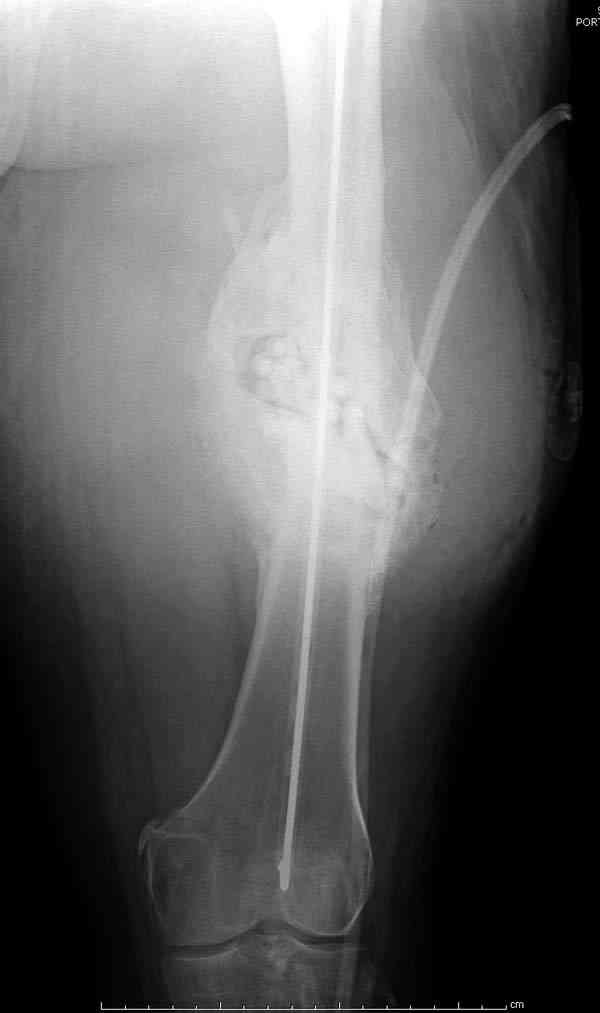

После нескольких некрэктомий, проведения аутодермопластики и заживдения ожоговой раны через 2 месяца после травмы произведен открытый остеосинтез левой бедренной кости штифтом и пластиной (деротационной) [image 01, 02]. Через 1 год и 7 месяцев после травмы у больного диагностированы ложный сустав и хронический остеомиелит левой бедренной кости. Произведено удаление металлических фиксаторов, секвестрэктомия и остеосинтез бедренной костивнешним двухплоскостным стержневым аппаратом [image 03, 04] .